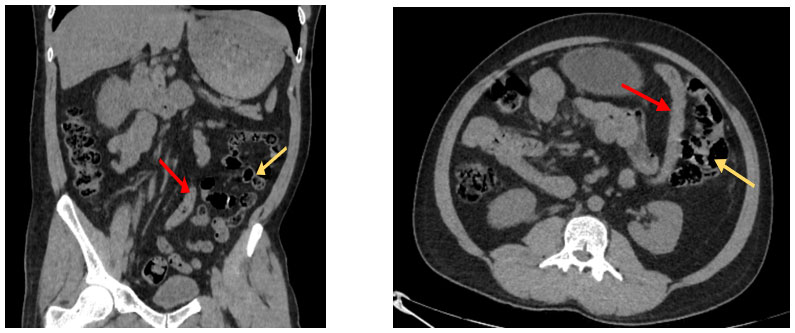

CT abdomen was performed, which revealed a right-sided inguinal hernia containing sigmoid colon, Mesocolon and omentum as content. There was mild fat stranding noted at the level of the deep inguinal ring, indicating early inflammatory changes.

An anatomical variation was observed with the small bowel loops located on the right side to a medially shifted descending colon — suggestive of a persistent descending mesocolon, a rare congenital anomaly due to failed fusion of the descending colon mesentery with the posterior abdominal wall.

Medially shifted descending colon (red arrow) with small bowel loops located on the right side to the later (Yellow arrow)

In this case, the sigmoid colon, which is normally fixed in the left lower quadrant, was found herniating through a right inguinal defect. The CT scan revealed small bowel loops located on the right to descending colon, supporting the diagnosis of PDM. This unusual orientation likely facilitated the abnormal transit of large bowel content toward the right groin, ultimately contributing to herniation.